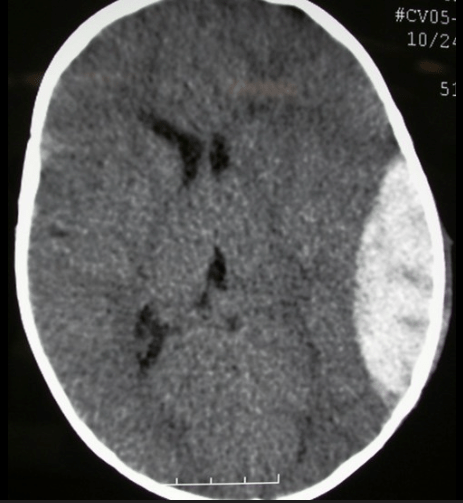

This is the finding on this CT.

What is subarachnoid hemorrhage?

This vasculature is involved in the injury present on this CT.

What is the Middle Meningeal Artery?